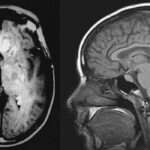

La intoxicación por bloqueadores beta-adrenérgicos es un fenómeno clínico complejo que se asocia a la administración excesiva o inadecuada de fármacos que actúan sobre los receptores beta-adrenérgicos del sistema nervioso…